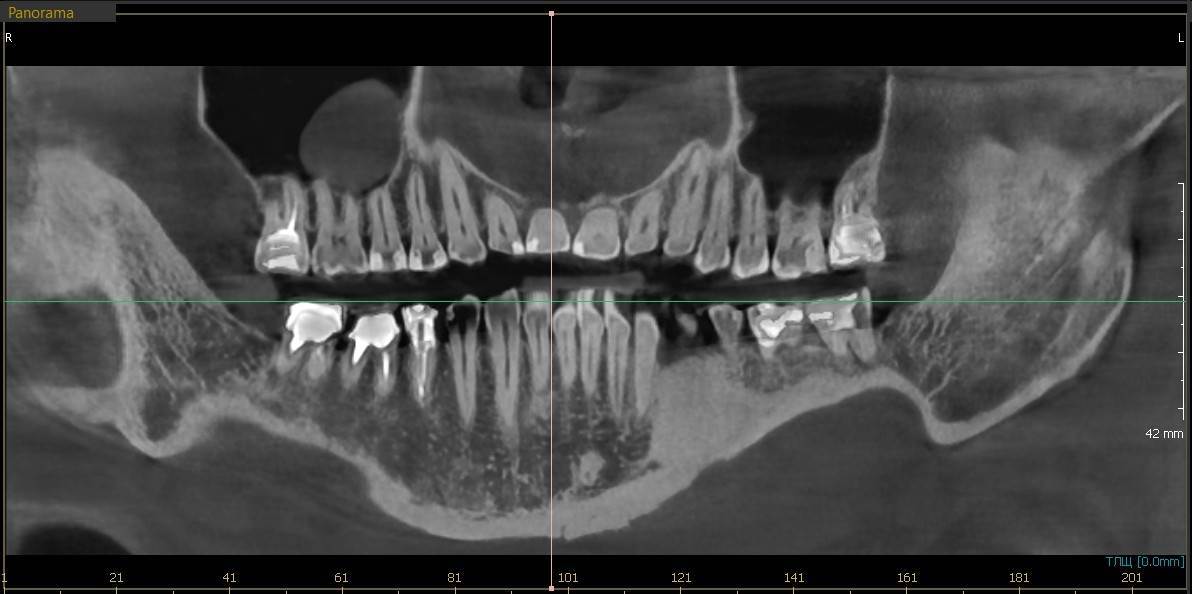

A-V-S Опубликовано 3 марта Поделиться Опубликовано 3 марта Здравствуйте. У меня такая ситуация: В начале января 2026 начал болеть зуб 7ка снизу слева - боль развивалась постепенно - в итоге стало больно жевать. Сделал КТ. Лечащий стоматолог сказал, что это проснулось спящее воспаление, перелечивать каналы зуба сложно - надо сверлить буром и доставать стекловолоконный штифт - надо удалять. В следующие дни открылся свищ и боль ушла. Свищ продолжает быть с периодическим набуханием и сдуванием после выброса гноя белого цвета. Этот зуб лечили с установкой стекловолоконного штифта чуть больше 5 лет назад. Посмотрите, пожалуйста, приложенные снимки и посоветуйте как быть - можно ли перелечить и сохранить зуб ? Ссылка на комментарий

АнтонТЛТ Опубликовано 3 марта Поделиться Опубликовано 3 марта Добрый вечер, лучше выложить несколько срезов этого зуба, либо архив с кт. По представленным снимкам, есть подозрение о наличии трещины между корнями зуба. 1 1 Ссылка на комментарий

Гарриевич Опубликовано 6 марта Поделиться Опубликовано 6 марта Не знаю обрадует Вас это или огорчит, но зуб можно сохранить соседний тоже с воспалением кстати 1 1 Ссылка на комментарий

red_butler Опубликовано 9 марта Поделиться Опубликовано 9 марта В 03.03.2026 в 22:49, A-V-S сказал: можно ли перелечить и сохранить зуб ? можно Ссылка на комментарий